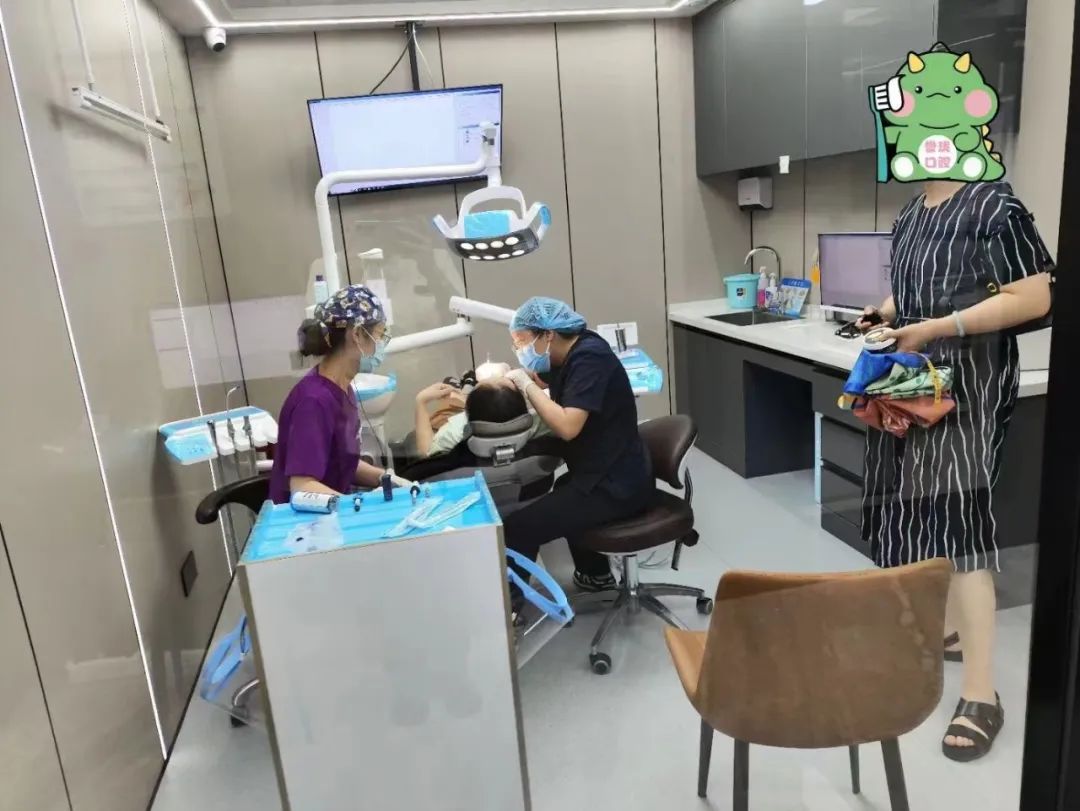

誉珑口腔诊所

专注致力于每个人的口腔问题

自成立以来,已经为很多人解除了牙疾之苦

作为优质品牌,秉承以技术为中心

以服务核心的品牌服务理念

集牙齿保健、修复、治疗为一体的

高水准、高规格的现代牙科机构

有着领先的管理体系以及专业设备

先进的设备+技艺精湛的医师

还你一个健康的口腔